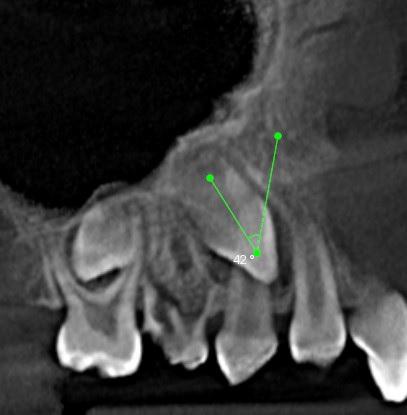

W żuchwie:

71,72,81 – zęby mleczne, wierzchołki korzeni skrócone.

Wykazują cechy resorpcji fizjologicznej.

81 71